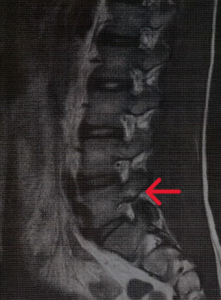

ところで木原選手は2023年に一時ケガで競技を離れていたことを皆さんはご存じでしょうか。病名は「腰椎分離症」です。スポーツ選手によく起こる腰椎の疲労骨折で主に第4または第5腰椎の椎弓という部位に起こります。発症年齢は若い年代に多く成長期に部活やクラブチームで過剰な練習で腰に負荷をかけすぎて発症することが多い疾患です。かくいう私自身も発症してしまいましたが… 野球やバスケ、サッカーなどの競技に起こりやすいと言われています。ちょっと分かりにくいですが、下のMRI写真の若干白くぼんやり光っている場所が分離部です。